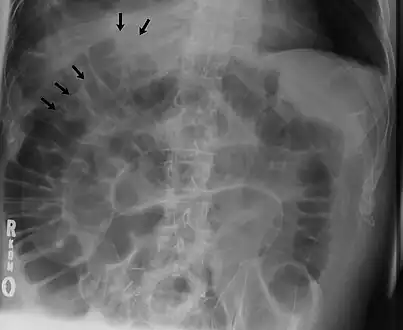

The double wall sign marks the presence of air on both sides of the intestine.[27] However, a false double wall sign can result from two loops of bowel being in contact with one another.[28] The sign is named after Leo George Rigler.[29] It is not the same as Rigler's triad.

The football sign is when the abdomen appears as a large oval radiolucency reminiscent of an American football on a supine projectional radiograph.[30] The football sign is most frequently seen in infants with spontaneous or iatrogenic gastric perforation causing pneumoperitoneum. It is also seen in bowel obstruction with secondary perforation, as in Hirschprung disease, midgut volvulus, meconium ileus and intestinal atresia. Iatrogenic causes like endoscopic perforation may also give football sign.

The Cupola sign is seen when air is accumulated under the central tendon of the diaphragm.[31]

a) X-ray of abdomen, showing subdiaphragmatic free air, air outlining the properitoneal fat stripe black arrows b) Cupola sign arrowheads c) Rigler's sign d) chest radiograph showing free air under the diaphragms

Double wall sign. This is a secondary sign of pneumoperitoneum. Patient is supine, and air within the abdomen and lumen of the bowel accentuate both sides of the bowel wall.- Ultrasound finding of pneumoperitoneum known as "peritoneal stripe sign"[32]